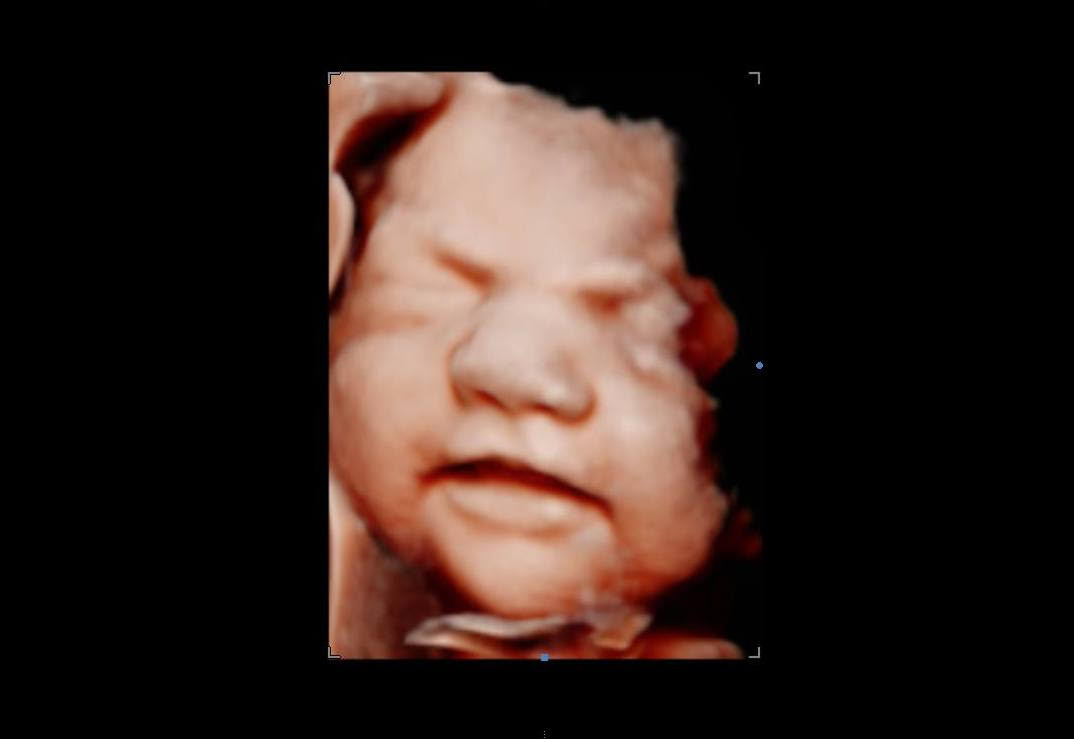

Browsing our 4D ultrasound photos gives you a clear idea of what your session can look like. You will see a range of images, from early 2D visits and gender reveal moments to rich 3D, 4D, and HD live facial detail captured during the most popular weeks between 26 and 32 weeks. Babies are unpredictable, but we have spent many sessions helping families get those sweet expressions, tiny stretched arms, and peaceful faces that you will want to hold onto for years.

Image clarity depends on factors like baby’s position, amniotic fluid levels, and gestational age. If your heart is set on detailed facial images, booking between 26 and 32 weeks gives you the best chance of seeing those fuller features and that characteristic stillness babies often have later in pregnancy.